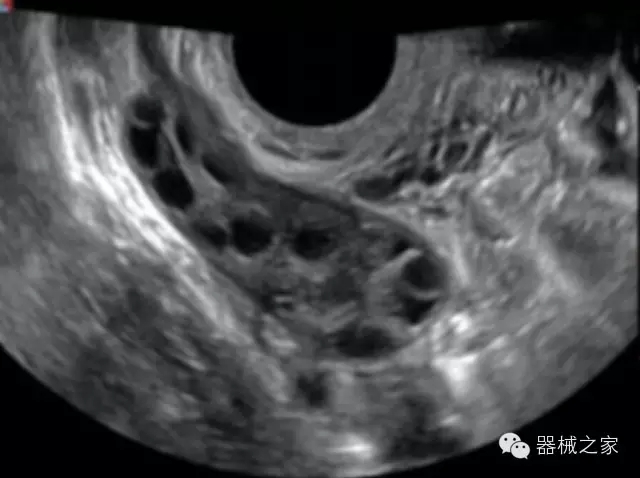

品牌:開(kāi)立(SONOSCAPE)

深圳開(kāi)立生物醫(yī)療科技股份有限公司作為中國(guó)民族醫(yī)療產(chǎn)業(yè)的優(yōu)秀引導(dǎo)者,自成立伊始,一直致力于臨床醫(yī)療設(shè)備的研發(fā)和制造,產(chǎn)品涵蓋醫(yī)用數(shù)字超聲診斷系統(tǒng)、電子內(nèi)窺鏡系統(tǒng)、全自動(dòng)五分類血液細(xì)胞分析儀以及自主研發(fā)的探頭群。

官方網(wǎng)站:www.sonoscape.com.cn

經(jīng)典產(chǎn)品:S8EXP

臨床圖片賞析

產(chǎn)品特點(diǎn)

優(yōu)異的成像技術(shù)

·亞陣元技術(shù):獨(dú)有的亞陣元技術(shù),對(duì)獨(dú)立晶片做二次切割,減少旁瓣偽像,增加臨床診斷的準(zhǔn)確性;

·μ-Scan微米成像技術(shù):開(kāi)立獨(dú)有的μ-Scan技術(shù),還原出真實(shí)細(xì)膩、層次對(duì)比優(yōu)異的二維圖像;

·倒相諧波成像技術(shù):倒相諧波技術(shù)在去除基波信號(hào)的基礎(chǔ)上獲取兩倍二次諧波信號(hào),提高組織圖像的對(duì)比分辨力;

·智能微血流成像技術(shù):智能微血流捕捉技術(shù)可以提取出隱藏在背景噪聲中的弱血流信號(hào),大大提高低速血流的敏感性;

全面的臨床解決方案

超聲科常規(guī)領(lǐng)域應(yīng)用

·移植S40高端臺(tái)式彩超高端平臺(tái)技術(shù),滿足超聲科腹部、淺表、婦產(chǎn)科、心血管、肌骨等應(yīng)用,提供超聲科完美解決方案;

·實(shí)時(shí)的彈性成像技術(shù):提高了小器管(乳腺,甲狀腺、淺表軟組織腫瘤等)疾病鑒別診斷;

·IMT血管內(nèi)中膜自動(dòng)測(cè)量:為血管性疾病評(píng)估提供了有效的評(píng)估手段;

·心功能綜合指數(shù)(TEI指數(shù)):用于左、右心室整體心臟收縮舒張功能評(píng)估的測(cè)量方法;

·全方位可調(diào)M型:有利于更好的觀察心腔大小及室壁階段性運(yùn)動(dòng)的異常情況;

·組織多普勒成像(TDI):TDI可定量評(píng)價(jià)心肌運(yùn)動(dòng),判斷是否有局部病變,還可評(píng)價(jià)早期的舒張功能;

·高效3D/4D成像技術(shù):高速的4D幀頻,豐富的3D成像模式,智能斷層切片功能;

POC領(lǐng)域解決方案

·外觀小巧;

·穿刺增強(qiáng)技術(shù):可有效提高進(jìn)針區(qū)圖像分辨率,提高進(jìn)針亮度,全面提高一次性穿刺的成功率;

全面的術(shù)中探頭解決方案

·小凸探頭:開(kāi)放性手術(shù),實(shí)時(shí)監(jiān)測(cè)病灶位置,提高手術(shù)成功率,可應(yīng)用于麻醉科、肝膽外科、腫瘤外科、神經(jīng)外科、泌尿外科等手術(shù);

·L型線陣探頭:高分辨率圖像,清晰顯示病灶位置,提高手術(shù)成功率,可應(yīng)用于麻醉科、胸外科、肝膽外科、腫瘤外科、神經(jīng)外科、泌尿外科等應(yīng)用;

·MPTEE:經(jīng)食道探頭術(shù)中監(jiān)測(cè),可測(cè)量心臟前負(fù)荷(左室舒張末期大小、右房大小)、心排血量、后負(fù)荷、收縮功能、室壁運(yùn)動(dòng)分析、肝靜脈血流(與中心靜脈壓相關(guān))等,術(shù)后還能及時(shí)評(píng)估手術(shù)效果評(píng)估;

·獨(dú)有的大角度及實(shí)時(shí)溫控技術(shù),能同一切面顯示宮頸及宮體,有效減低了患者的痛苦,及保護(hù)粘膜保證了醫(yī)療安全;

高效的人機(jī)工程學(xué)設(shè)計(jì)

·15‘’高清醫(yī)用顯示器;

·內(nèi)置雙探頭接口;

·可升降臺(tái)車,1拖3探頭擴(kuò)展器;

·m-Tuning一鍵優(yōu)化;

CFDA注冊(cè)證編號(hào)

·粵食藥監(jiān)械(準(zhǔn))字20132230491